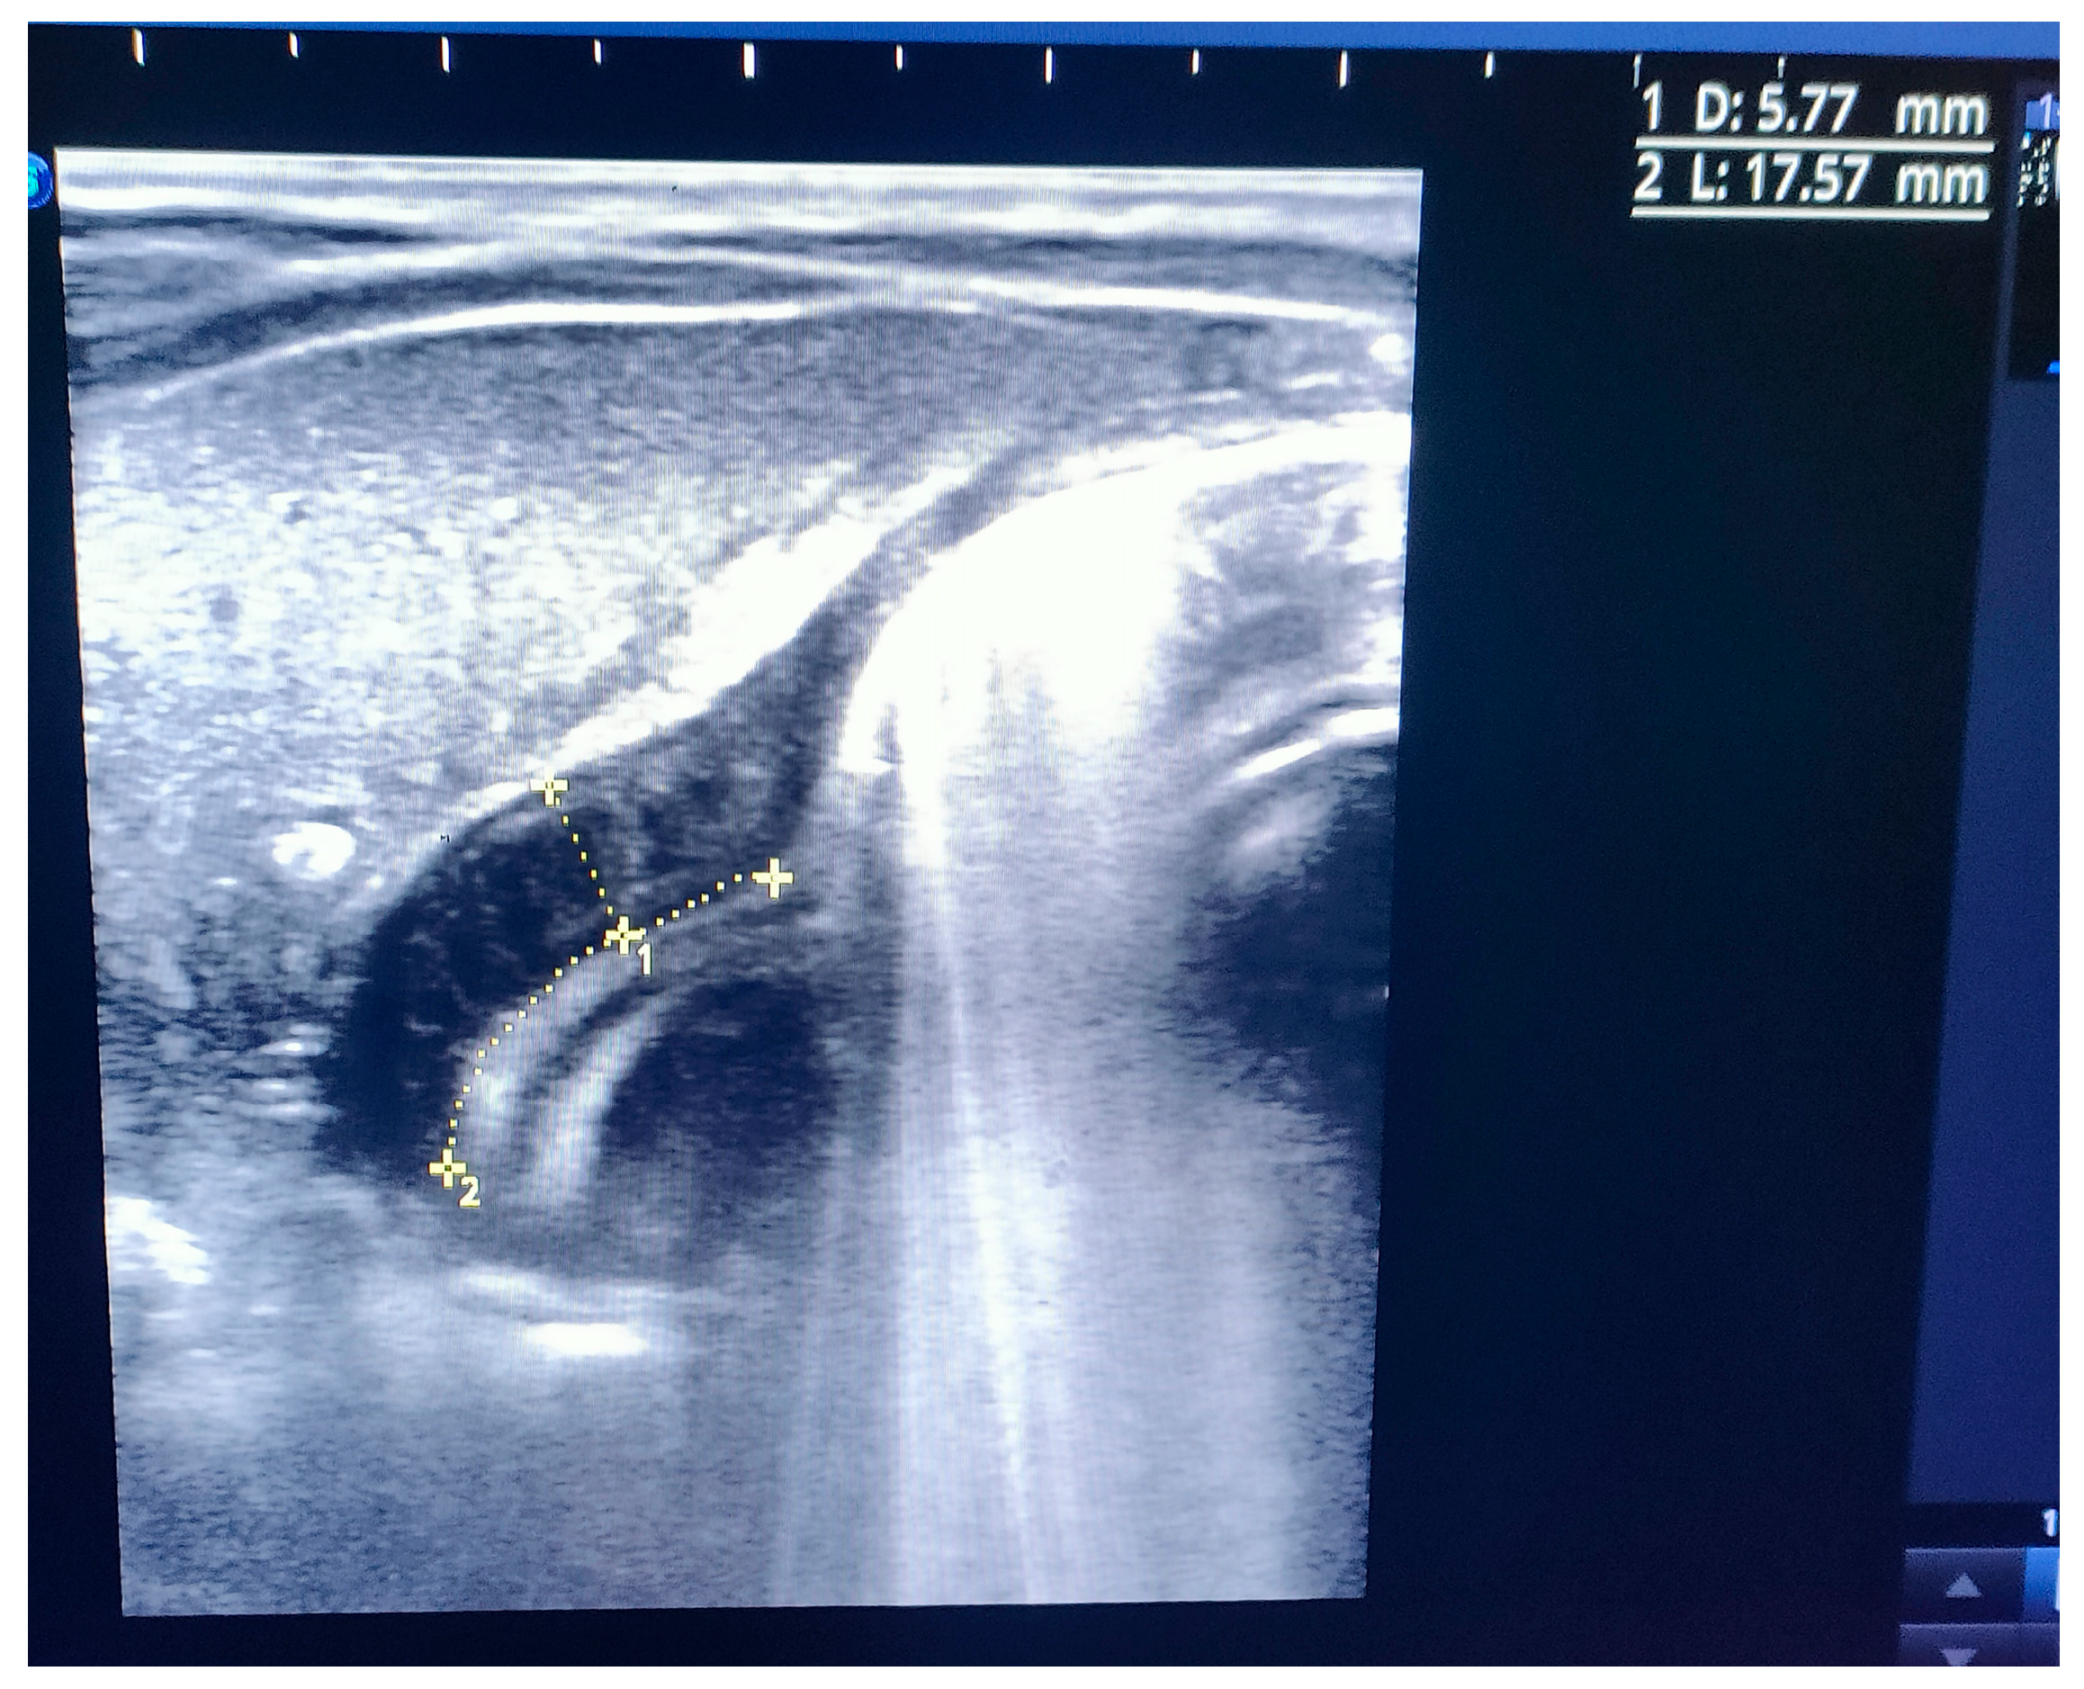

After admission, the infant presented with some projectile, non-bilious vomiting. An abdominal X-ray proved a marked gastric distension (Figure 1). An abdominal ultrasound (US) displayed a thickened pylorus with a wall thickness of 5.7 mm and a length of 17.5 mm (Figure 2). A diagnosis of hypertrophic pyloric stenosis was made.

Figure 2. First ultrasound image indicating pyloric hypertrophy. The image displays the initial measurement of the pyloric muscle thickness ( 5.77 mm).